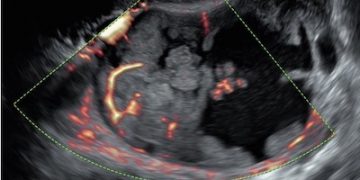

How To Do Luglio 2023: terminologia e classificazione MUSA

Cari soci, questo mese un nuovo video "How to do", dedicato alla terminologia e classificazione MUSA Grazie a Francesca Arezzo! Il video è accessibile ai soli soci SIEOG attraverso questo...